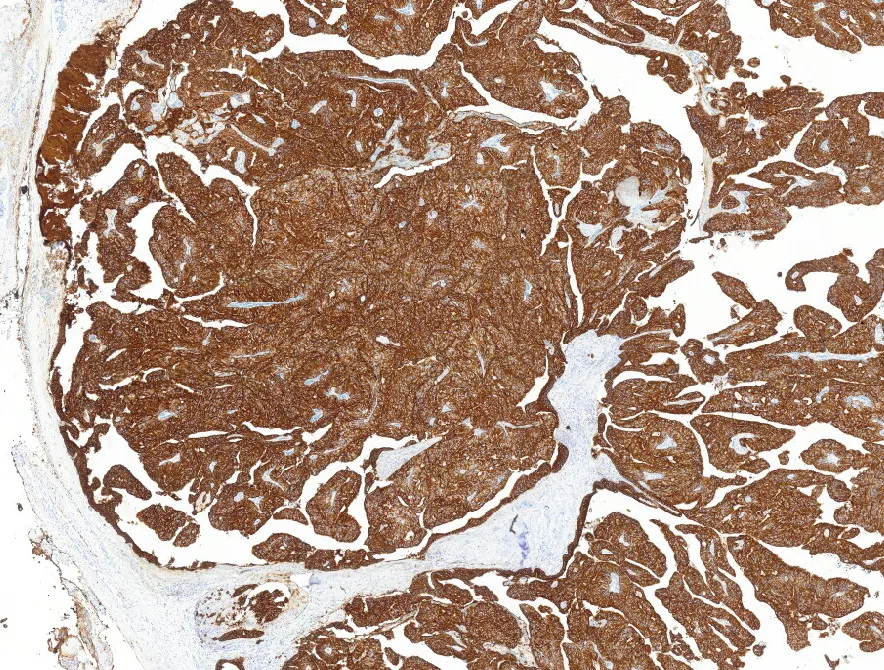

7-CK7

- Histológicamente se caracterizan por áreas quísticas y sólidas con múltiples proyecciones papilares luminales que tienen un núcleo fibrovascular y están revestidas por células epiteliales cúbicas, columnares o secretoras de moco. Inmunohistoquímicamente es CK7, CEA y EMA positivo, siendo negativo para otros marcadores de glándula salival. (PMID: 35252049)